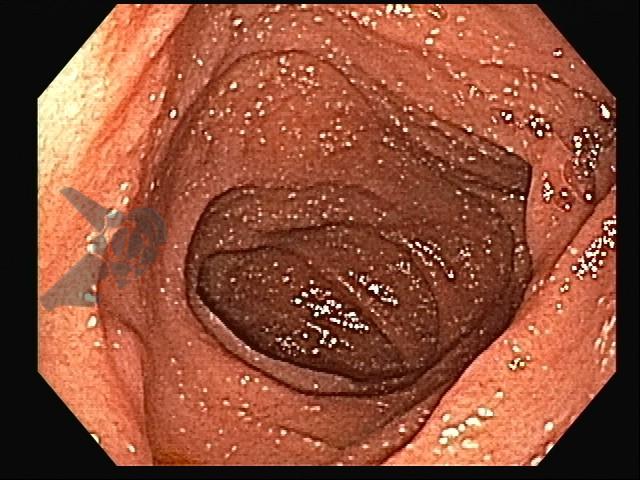

Paciente do sexo feminino, 47 anos, com história de artralgia migratória intermitente há 1 ano, queixa-se de diarreia crônica, dor abdominal e perda de peso não intencional há 3 meses. Na investigação, a Endoscopia Digestiva Alta evidenciou mucosa duodenal com áreas de vilosidades edemaciadas e presença de múltiplas placas esbranquiçadas elevadas. A avaliação histopatológica das biópsias duodenais demonstrou expansão da lâmina própria por macrófagos espumosos positivos para a coloração de Ácido Periódico de Schiff (PAS) e resistentes à diástase. A coloração de Ziehl-Neelsen resultou negativa.